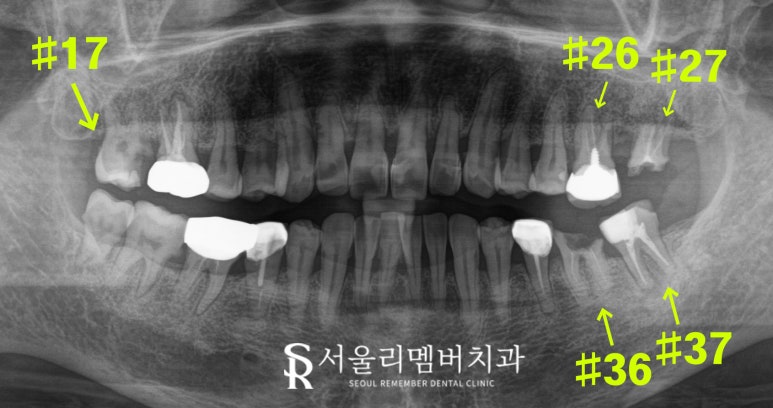

전체 구강 검진을 진행한 결과,

다음과 같은 문제들이 발견되었습니다.

1️⃣ #17번: 심한 충치로 이가 깨져 있었습니다.

2️⃣ #26번: 오래된 보철이 깨져 교체가 필요했습니다.

3️⃣ #27, 36번: 이가 부서져 치근만 남아있었고,

치근우식이 심한 상태였습니다.

4️⃣ #37번: 치주낭이 깊었지만 자연치 보존을 위한

개선책을 생각할 필요가 있었습니다.